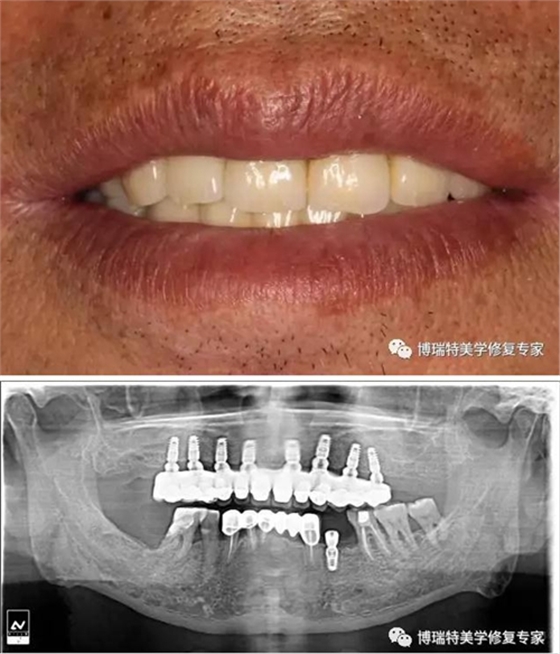

螺絲固位基臺修復(fù)便于操作,但程序相對復(fù)雜,比較普遍的還是使用二次印模法完成,大致流程如下:

患者口內(nèi)閉合式轉(zhuǎn)移桿取模,托盤和替代體送技工所;

技師完成石膏模型的翻制;在石膏模型上安裝開窗轉(zhuǎn)移桿,并通過樹脂將開窗轉(zhuǎn)移桿連接到一塊;

用樹脂連接的開窗轉(zhuǎn)移桿寄回門診;

醫(yī)生從連接兩個(gè)開窗轉(zhuǎn)移桿的樹脂中間處切斷,并把每個(gè)轉(zhuǎn)移桿依照模型上的排列單獨(dú)在患者口內(nèi)安裝到位。再次使用樹脂將轉(zhuǎn)移桿連接。這些工作主要是為了確保取模的準(zhǔn)確性;

二次取模完成的印模寄給技工所,技師在此基礎(chǔ)上完成最終模型,并在此模型上完成上部冠的制作,義齒制作完成后寄回門診;

醫(yī)生完成最終修復(fù)體的安裝。